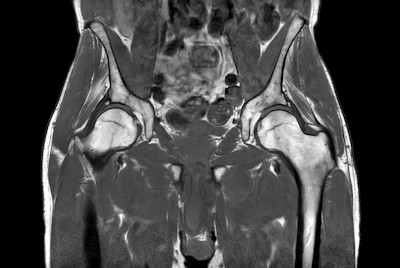

Fast bilateral hips, with SmartSpeed Precise